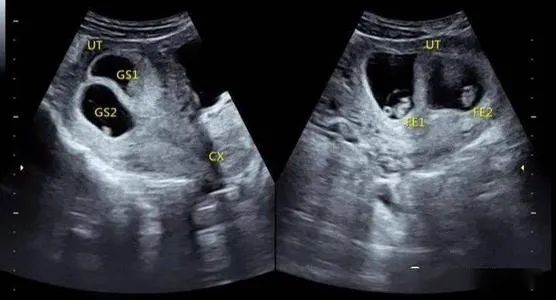

●双胎妊娠检查非常重要:

由于双胎孕妇比一般孕妇子宫明显增大,这不仅增加了孕妇身体的负担,还由于对其心、肺及下腔静脉的压迫而容易产生心慌、呼吸困难及下肢浮肿等不适。双胎妊娠出现妊娠合并症者也较多,其妊高娠的发生率明显高于一胎妊娠,所以双胎妊娠者要听从医嘱,按期去医院接受检查。